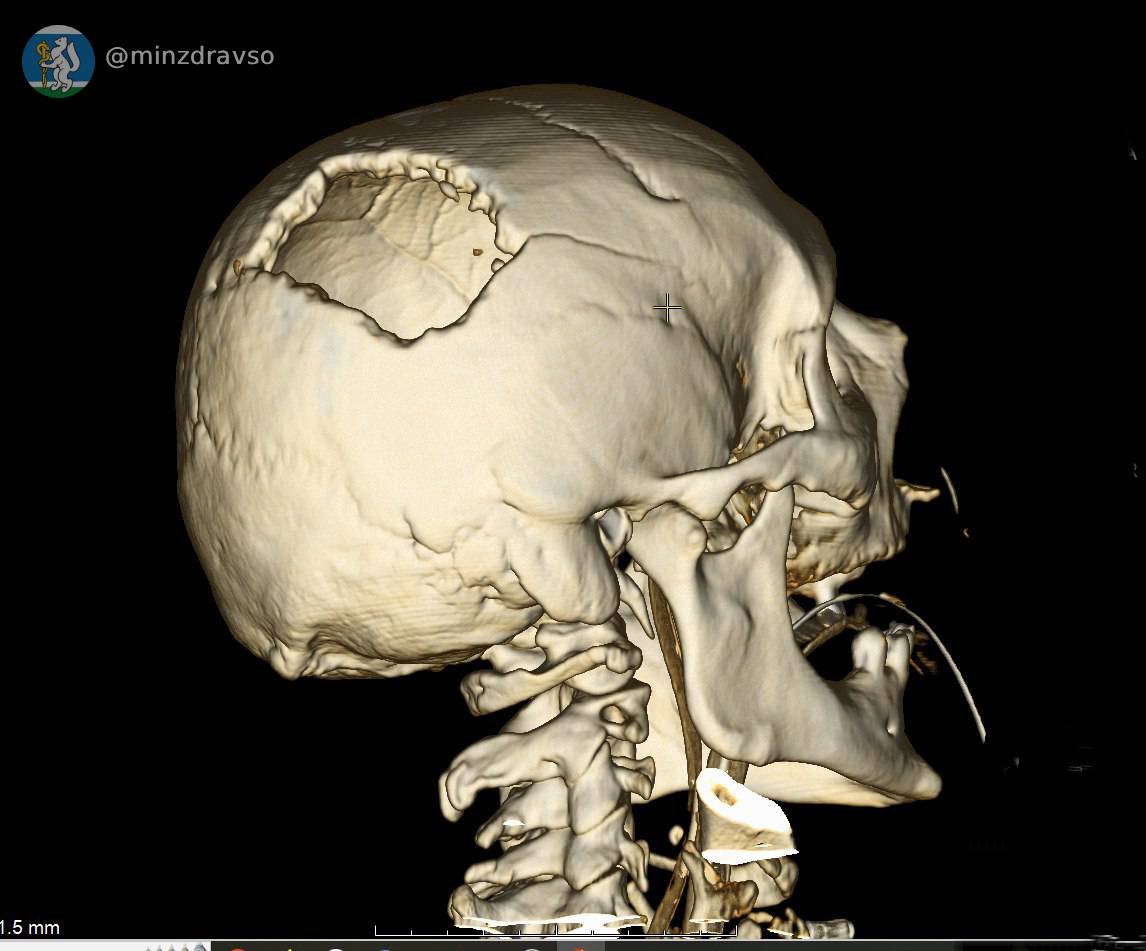

В Серове 57-летнего мужчину ударила стрела строительного крана, расколов ему череп. В критическом состоянии мужчина поступил в единственное на севере нашего региона стационарное отделение скорой медицинской помощи, действующее на базе Серовской городской больницы. Высокоточный компьютерный томограф помог быстро диагностировать травмы и выявить расположение повредивших мозг костных отломков, самый острый из которых мог в любую минуту стать причиной гибели пациента. Слаженное взаимодействие серовских реаниматологов позволило стабилизировать состояние пострадавшего.

Профильные специалисты из Екатеринбурга в ходе телеконсультации подтвердили необходимость перегоспитализации уральца в ближайший межмуниципальный медицинский центр. Мужчину экстренно доставили в Городскую больницу №1 Нижнего Тагила, где его ожидала операционная бригада. Нейрохирург Дмитрий Неволин, анестезиолог-реаниматолог Аслам Абдуев и операционная медсестра Нина Дмитриева удалили отломки костей, гематомы, восстановили целостность твёрдой мозговой оболочки.